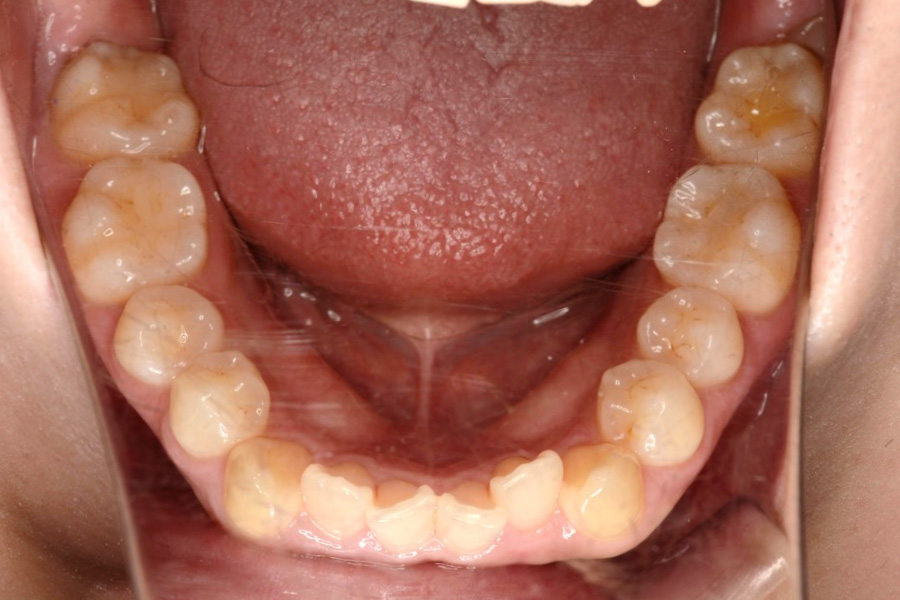

【20代女性】

全体のガタつきを

インビザライン矯正で治療したケース

治療前

主訴 全体のガタつきが気になる

治療内容 インビザライン矯正

非抜歯